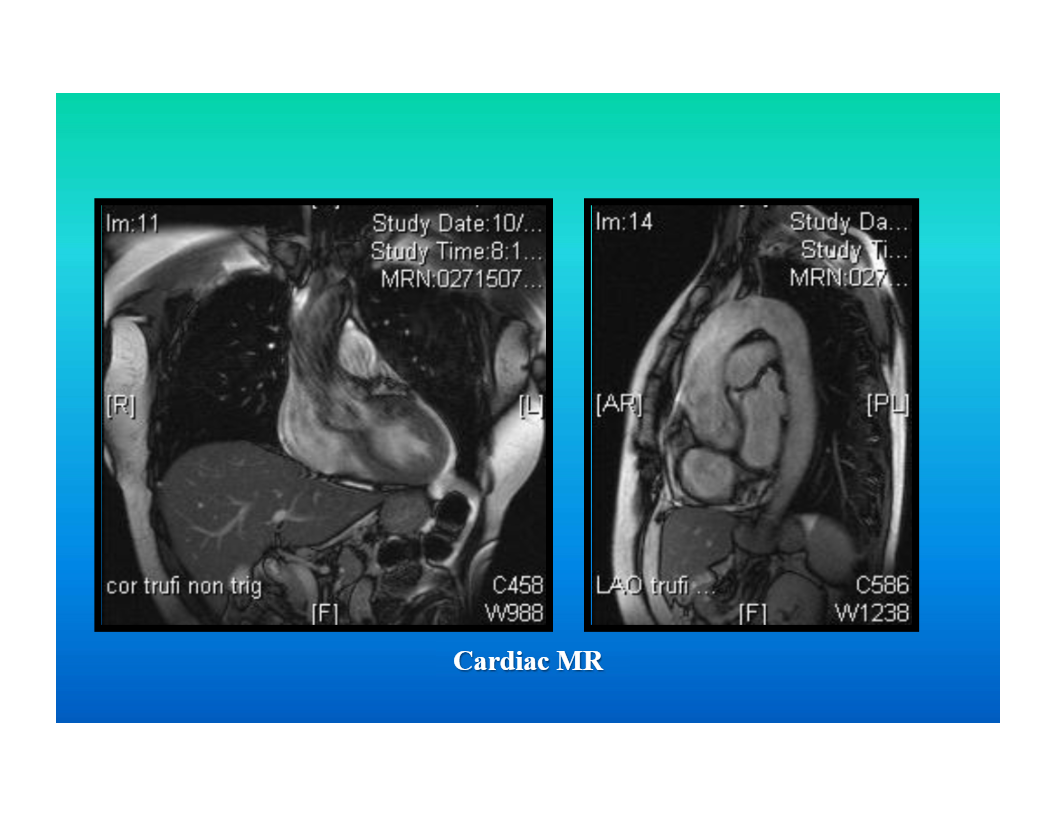

magnetic resonance imaging

computer generated image obtained by placing patient in a magnetic field and applying a radiofrequency pulse to change alignment of hydrogen protons

may use intravenous contrast (gadolinium)

image descriptor is signal

tissue caracterized with different pulse sequences

multiple scan planes possible